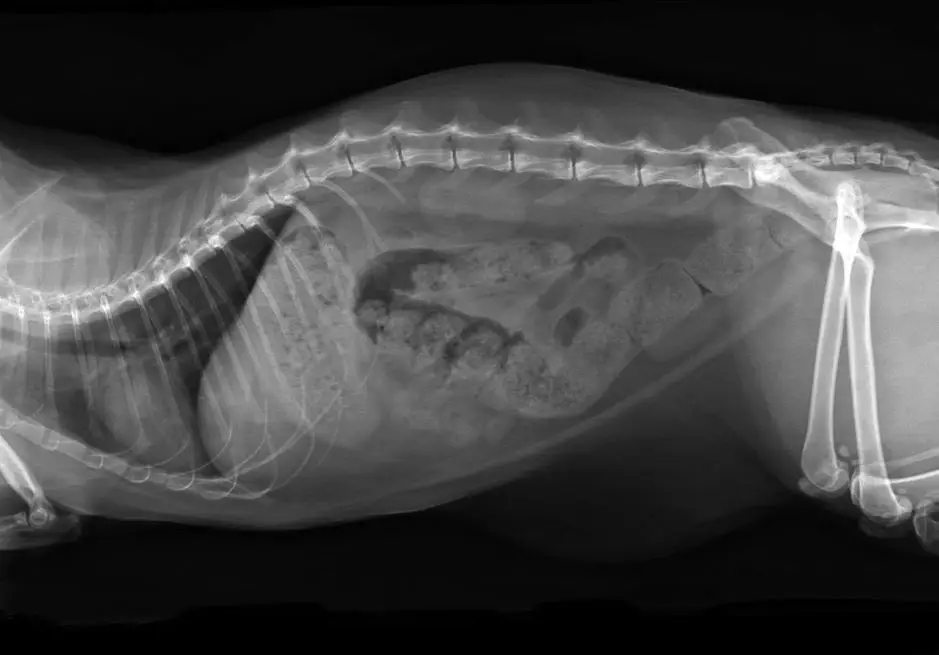

Ez a fenti radiográfia komoly székrekedést mutat

Egyes esetekben az állatorvos képeket készíthet egy akadály vagy Megolon bizonyítékának ellenőrzésére.